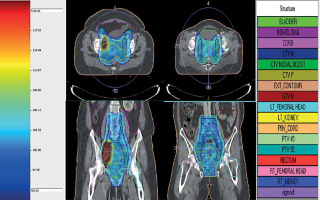

IMRT planning constraints used for target coverage were as follows: 95% prescription isodose surface to encompass ≥ 95% of PTV and maximum dose of ≤ 107% (contained within PTV). Dose constraints for normal tissues were as follows: (1) Bowel bag: volume receiving 40 Gy (V40Gy) < 100 cc and 30 Gy (V30Gy) < 350 cc. In cases of nodal boost, V40Gy < 250 cc and V30Gy < 500 cc; (2) Rectum: V40Gy < 85% and V30Gy < 95%, Dmax < 105% (in case of IIIC1 patients); (3) Bladder: V40Gy < 75%, and V30Gy < 85%, Dmax < 105% (in case of IIIC1 patients); (4) Femoral heads: maximum dose (Dmax) ≤ 50 Gy; (5) Sigmoid: maximum dose ≤ 48 Gy. Plans were evaluated using dose-volume histograms (DVH), planar isodose display, and 3D isodose display (Figure 1). Conformity index (TV ref [total volume covered by the referenced isodose]/TV [volume of total PTV]), and homogeneity index (D2% [dose received by 2% volume of PTV]/D98% [dose received by 98% volume of PTV]) were also evaluated. Treatment was delivered using Elekta Infinity linear accelerator, with MLC leaf width of 1 cm at the isocenter by volumetric modulated arc therapy (VMAT). Treatment verification was performed daily with kV-CBCT before treatment in all patients, and on-line corrections were made prior to treatment delivery. Concurrent chemotherapy was given with weekly intravenous cisplatin of 40 mg/m2. Dose was modified according to weekly assessment of creatinine clearance level.

The median coverage of 95% of PTV by 95% of prescribed dose was 99.18% (range, 96.85-99.80%). The median conformity index and homogeneity index were 0.98 (range, 0.96-0.99) and 0.95 (range, 0.93-0.96), respectively. DVH parameters for OARs are presented in Table 2. The median dose to 98% of PTV, 2% of the bladder, 2% of the rectum, and 2% of the sigmoid colon were 42.8 Gy (range, 42.3-43.4 Gy), 45.6 Gy (range, 45.3-47.8 Gy), 45.2 Gy (range, 45.1-46.2 Gy), and 47.9 Gy (range, 46.3-48.8 Gy), respectively.